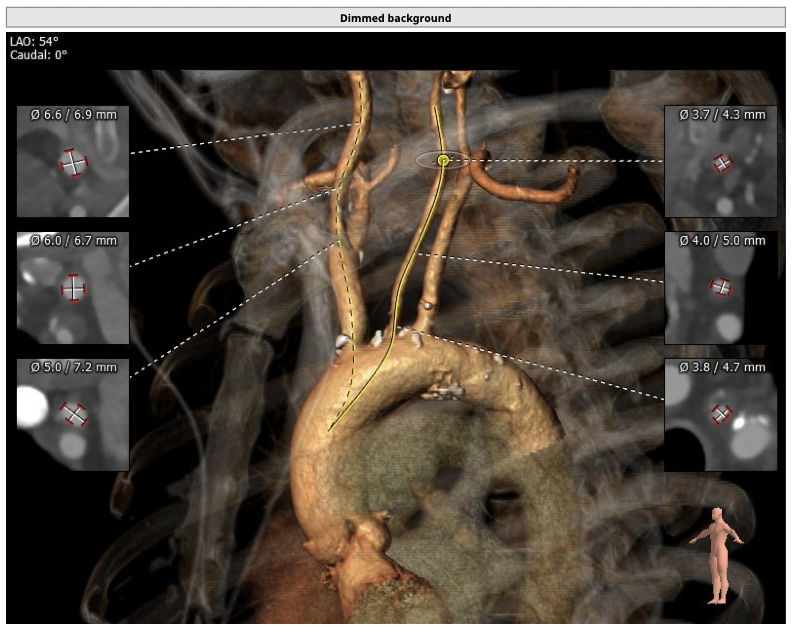

CT检查

①患者因规律透析导致钙磷代谢紊乱,外周血管斑块钙化严重,最狭窄处仅2.8mm,通路建立难度极大(左右颈动脉均不符合入路条件);

②主动脉根部钙化较轻,瓣叶肥厚,各交界缘不同程度粘连,瓣膜释放后具有瓣周漏风险;

③左冠高度不高,且瓣叶冗长,达冠脉开口层面,且冠脉存在狭窄,存在冠脉阻塞的风险;

确保冠脉安全,拟采取PCI+TAVR一站式手术策略,因患者右侧股动脉钙化严重、入路狭窄,拟采取无鞘法从右股动脉穿刺入路,选用20mm球囊预扩、L23号VenusA-Valve瓣膜、采用VenusA-Plus输送系统确保瓣膜的精确释放,瓣膜释放后结合造影和超声情况,决定是否后扩。